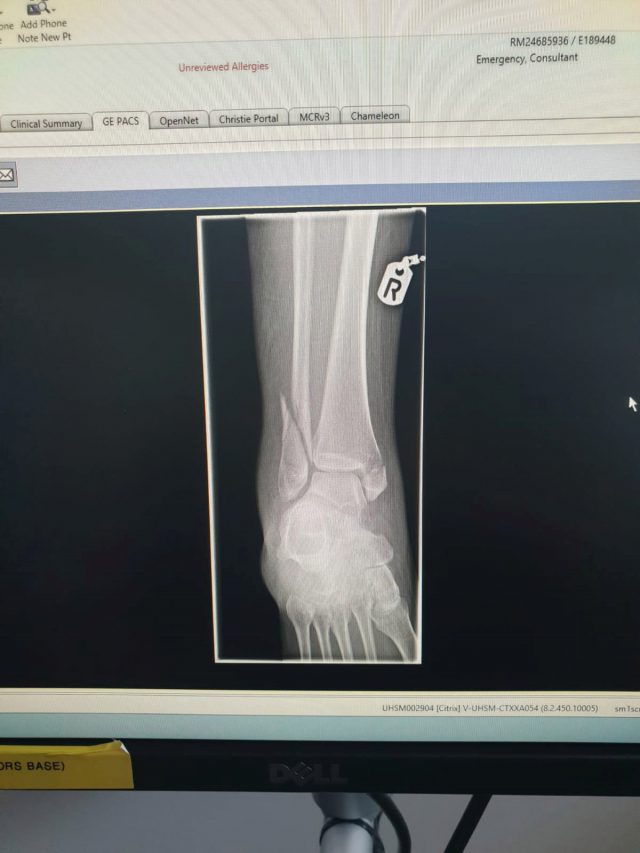

Como consecuencia del movimiento, la azafata cayó al suelo y el carro aplastó su pierna partiéndola por cinco partes, la tibia, y el tobillo. Garrity tuvo que esperar siete horas antes de ser atendida en un hospital en Manchester.